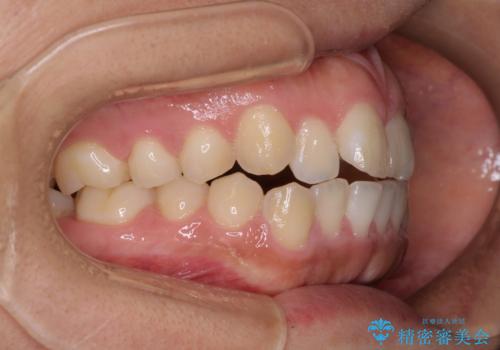

- 口が閉じにくさを気にして来院された患者様です。

上下の前歯が前方に突出していたため、上下左右の第一小臼歯4本を抜歯し、ワイヤー装置にて抜歯矯正を行うこととしました。

上下前歯部の被蓋関係を改善するの時間がかかり、3年間を要することとなりましたが、スッキリとした口元に仕上がりました。